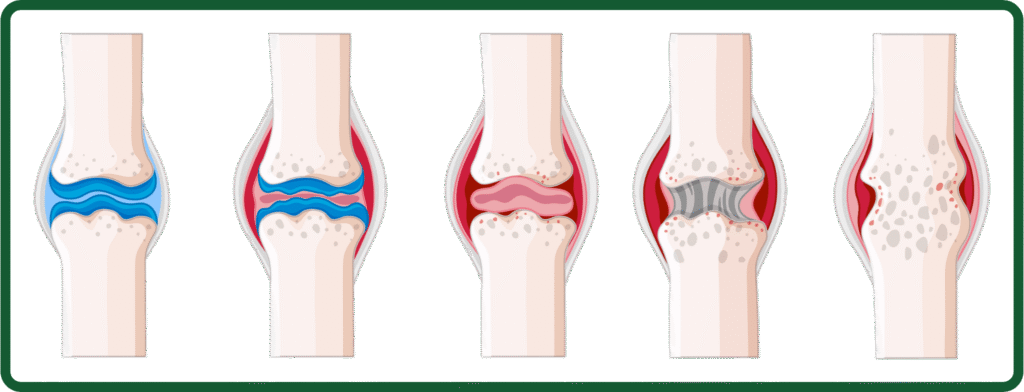

Knee arthritis is a leading cause of knee pain for adults over 40. The most common type, osteoarthritis, occurs when the smooth cartilage within the knee wears away and bones begin rubbing together causing pain, swelling, and stiffness. Other types include rheumatoid arthritis and post-injury arthritis, both of which may impact your knee health.

- Osteoarthritis (OA): The most common form, where protective cartilage gradually breaks down from wear and tear.

- Rheumatoid Arthritis (RA): An autoimmune disorder where the immune system attacks the joint lining, causing inflammation and damage.

- X-rays: To assess cartilage and joint space.

- MRI scans: For detecting early arthritis or soft tissue injury.